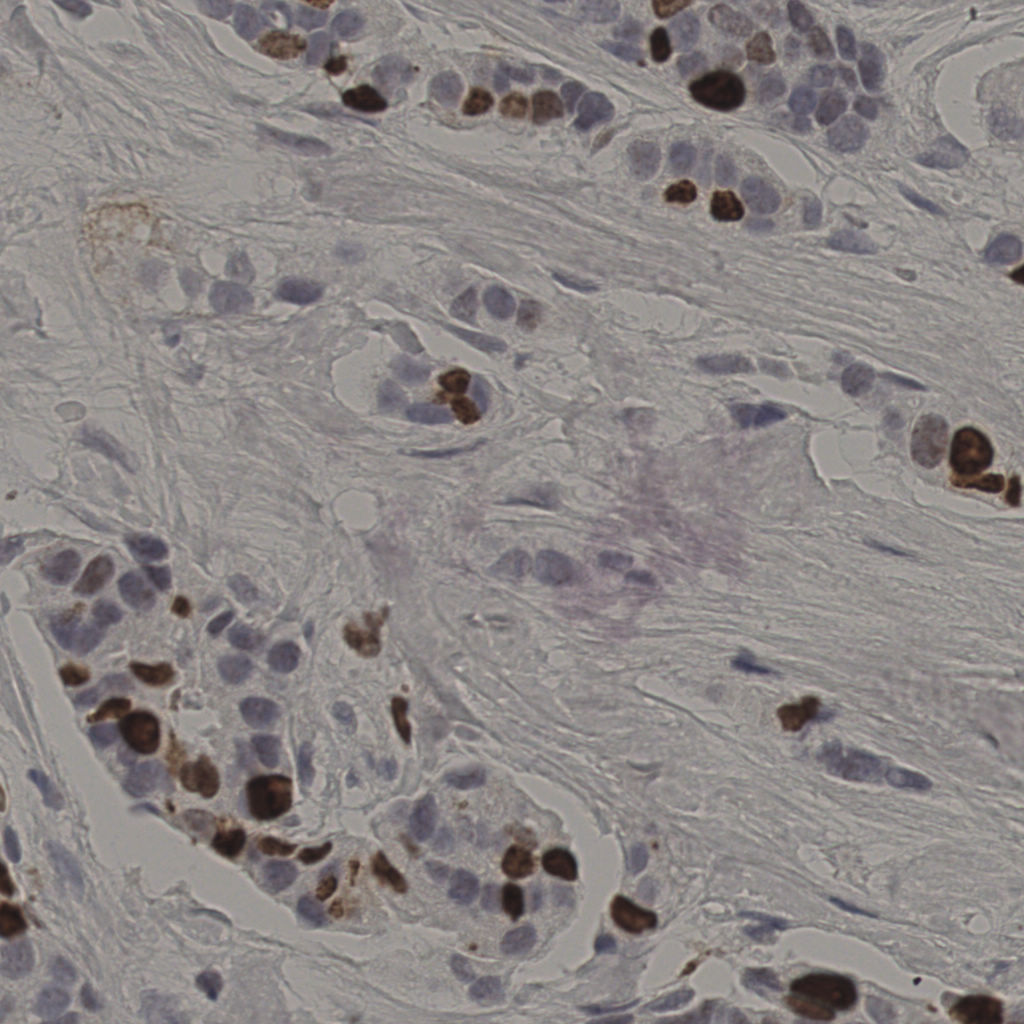

17.75%

Ki67 指数

阴 7986

阳 1723

切片统计

总切片

2640

有效

412

已标记

412

有效率

16%